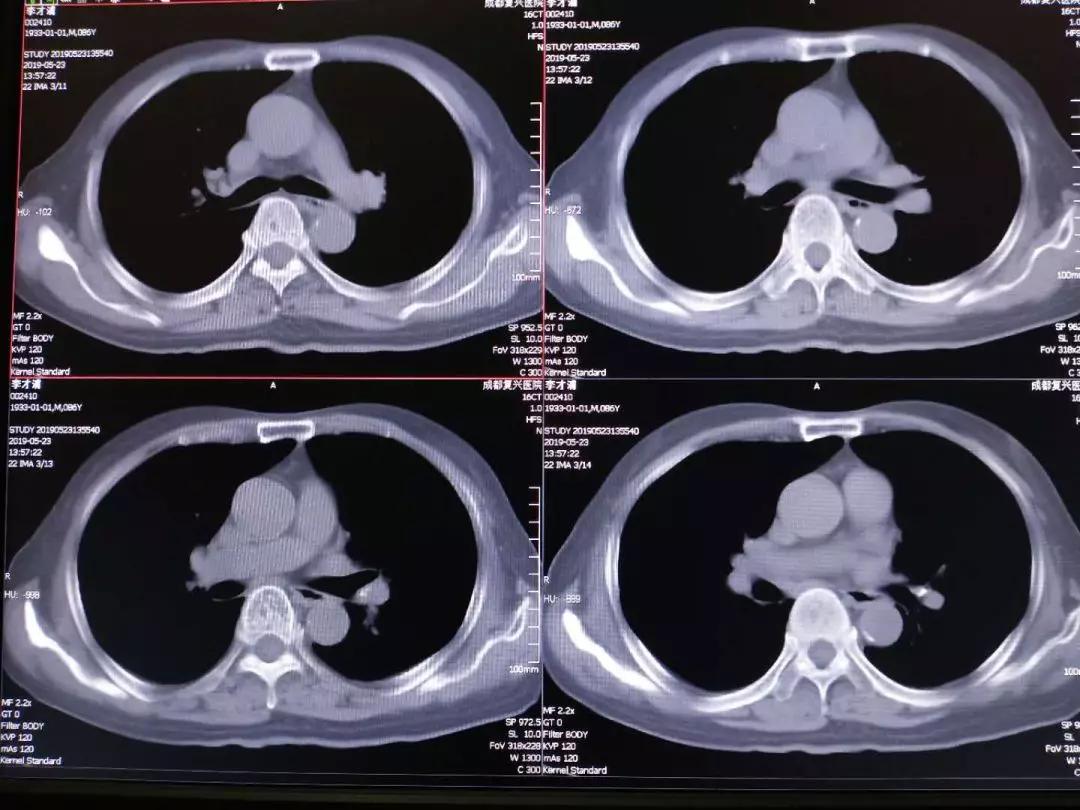

肺癌图片与正常肺图片[b0]肺部肿瘤是指发生在肺部的异常新生物分为良性肿瘤和恶性肿瘤两大类[b1]肺肿瘤和肺癌的图片肺癌长在肺叶上吗左肺囊肿是什么意思七七岁肺癌[b2]微创介入显身手不开刀消灭肺肿瘤[b3]全网资源[b4]肺肿瘤的恶性程度不能单凭大小判断[b5]肺肿瘤5cm良性几率多大当得知肺肿瘤长到5cm这样的尺寸时患者的内心[b6]老年男性右上肺结节大小16厘米手术明确浸润性腺癌老[b7]中央型肺部鳞状肿瘤能否实现治愈[b8]肺鳞癌术后复发[b9]肺上长了肿块不一定都是肺癌75岁女性2月来胸闷当地[b10]肺部病灶通过立体定向放疗之后这个肿瘤一个月之后复查已经消失了[b11]肺腺癌知多少一文带你揭秘这个肺事[b12]肺早期肿瘤究竟有多大一文读懂[b13]肺癌恶化最快的三种癌是什么肺癌是肺部的一种恶性肿瘤疾病这种疾病[b14]就是我们超过5个厘米以上的这个肺部的肿瘤我们可以先通过微创介入[b15]肺上长了肿瘤并不意味着无药可救哦首先要明确肿瘤的性质是列栽[b16]一个53岁肺腺癌晚期的病例[b17]拒绝化疗选择精准微创[b18]纵隔肿瘤严重吗是不是癌症[b19]面对体检报告上的肺结节10mm很多人心中都会升起一丝担忧这个[b20]右肺两个恶性肿瘤病人不能趴着只能躺着穿刺针刚刚好微[b21]左肺巨大肿瘤的临床决策思路分享[b22]肺部肿瘤知多少良恶性质大不同[b23]肺上有肿瘤是什么病严重吗[b24]年初手术成功实施粒子精准覆盖肿瘤区域[b25]肺鳞癌知多少一文带你全面了解[b26]肺早期肿瘤大小有讲究[b27]我院这位住院患癌的患者是得了周围型的肺部患癌而且肿瘤还侵犯[b28]6mm的肺结节在影像学上是一个相对较小的发现可能是良性的也可能[b29]患者胸背疼一个月做了ct发现肺上大肿块病理为浸润性肺腺癌[b30]5个层面讲清楚肺癌医学科普[b31]肺小结节和大肺癌有很大的区别[b32]6厘米有肺血管穿行图1并且血管有增粗[b33]肺结节是肺部影像学上的一种表现可能由炎症感染良性肿瘤等多种[b34]肺结节与肺癌的关系别再被误导了[b35]这类肺结节基本不复发[b36]得了肺癌要科学治疗这位老大伯用药两次肿瘤明显缩小家人[b37]简述常见良性肺肿瘤及其影像学特点[b38]一个不起眼的肺结节长成一个大肿瘤其实是很[b39]肺腺癌和肺鳞癌到底有哪些区别[b40]肺部鳞状细胞癌的一般存活年限是多少肺部鳞状细胞癌是一种非小细胞[b41]不开刀消灭肺肿瘤微创介入治疗快准狠[b42]患者因为胸痛就诊河津市人民医院行ct检查发现肺上长了个肿瘤[b43]瑞金胸外病例拾萃10肺类癌的诊治[b44]肿瘤2点5公分肺癌属于几期当发现肺部有一个2[b45]肺癌ct影像全解析带你读懂肿瘤信号[b46]重燃患者生命之光山东省第二人民医院肿瘤内科联合多学科精准施治肺巨[b47]12mm肺结节是肺癌几期你了解多少[b48]2cm部分实性结节恶性张力高病理浸润性肺癌磨玻璃[b49]肺结节的原因多种多样可能是由感染炎症良性肿瘤恶性肿瘤等导致[b50]202487天津医科大学总医院肺部肿瘤外科副主任医师[b51]肺结节和钙化灶是肺癌的前兆吗[b52]肺鳞癌是什么癌症[b53]2024516天津医科大学总医院肺部肿瘤外科副主任医师[b54]1肿块体积显著增大晚期肺癌的肿瘤体积[b55]肺结节癌变前可能出现的6种表现抖出健康知识宝藏[b56]肺结节早期肺癌一文解读肺部ct报告[b57]肺癌是恶性肿瘤疾病随着病情的发展可能会导致癌细胞出现远处转移[b58]1厘米的肿瘤[b59]

这个月的复查结果糟透了,肺上肿瘤疯长,已经发生了一次咳血。现在没有[s0]射波刀后肿瘤会消失吗[s1]是不是做了肺部穿刺就一定是肺肿瘤或者肺癌?[s2]图片[s3]肺上长肿瘤严重吗 小红书[s4]肺上良性肿瘤怎么办才能消除[s5]确诊为肺癌晚期。医生告知王阿姨,肿瘤发展较快,手术治疗的机会不大。[s6]后,医生的诊断结果让所有人震惊——是肺部恶性肿瘤,且已经是晚期了。[s7]右肺尖肿瘤,16个月迅速长大[s8]吸烟30年,虽已戒烟5年,但这个患者的肺黑得吓人,肺上的恶性肿瘤更加触目惊心![s9]岳母肺部肿瘤病情演变[s10]肺部肿瘤[s11]新方法可能减少肺部肿瘤的生长[s12]微信图片_20190404112215.jpg[s13]胸部肿瘤综合治疗之一肺癌篇~~~科大二附院胸外科胡举副主任医师治疗体会[s14]考虑肺部肿瘤[s15]肺部的恶性肿瘤[s16]肺部肿瘤[s17]右肺上叶肿瘤,穿刺难度大,患者高龄基础疾病多,手术中并发症风险大。[s18]麻烦给看一下我的肺部有肿瘤吗?谢谢了?[s19]肺上肿瘤切除手术好做吗(肺部肿瘤位置尴尬)(1)[s20]肺部巨大肿瘤[s21]少见!6厘米巨大肺部肿瘤—兖矿新里程总医微创切除![s22]查发现患者肺部也有一个肿瘤,考虑患者原发肿瘤在肺部,脑部是转移瘤。[s23]右肺上叶贴水平裂的肿瘤,手术切除范围的考量(病例回顾)[s24]肺部长肿瘤的症状[s25]这是一名35岁女性,左肺上叶将近4厘米的肿物,没有任何症状,查体时才发现,4厘米的肿瘤都没有临床症状,还是很可怕的。腔镜下切除,淋巴结应该不至于有转移,还是略偏早期,但术后是需要靶向药物治疗或者化疗的,尽量降低复发概率。所以,肿瘤不能等有了症状再就诊,分期晚了医生也没有办法。[s26]以前照片[s27]患者高龄基础疾病多,手术中并发症风险大。术前ct见右上肺肿瘤术中操作[s28]肺肿瘤影像大汇总,看完深刻理解[s29]发展,甚至肺上的肿瘤已经缩小了百分之四十,于是在2019年1月3日出院了。在进行了四个疗程的治疗后,[s30]肺上长肿瘤严重吗 mip.haodf.com[s31]肺上长肿瘤严重吗 来自网易[s32]右肺尖肿瘤,16个月迅速长大[s33]肺肿瘤有哪些危害[s34]肺肿瘤[s35]肿瘤标记物虽然是正常的,但是咳嗽原因不明,ct却发现肺上长了肿物.[s36]肺部恶性肿瘤需要手术吗能治好吗[s37]肺上长了肿瘤必须要做穿刺检查吗?[s38]肺部肿瘤能治好吗[s39]